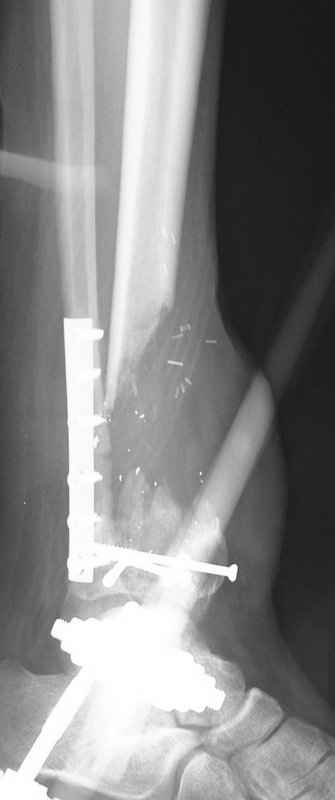

1 - рентгенограмма (прошу прощения за качество) при поступлении;

Произведено ПХО, acute shortening (5 см), фиксация стержневым аппаратом Hoffman.